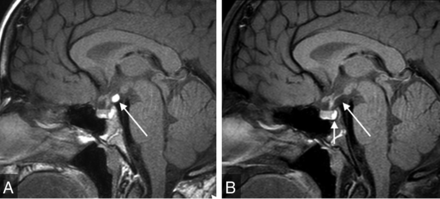

Microadenomas are a common-but-controversial justification for contrast administration in pediatric pituitary MR imaging and are often cited as a reason to include sequences such as dynamic contrast-enhanced images.21 They are seldom clinically relevant without signs and symptoms of hormonal hypersecretion (eg, galactorrhea, hyperprolactinemia). In addition, there are multiple pitfalls associated with imaging diagnosis. First, normally occurring hypoenhancing regions within a heterogeneously enhancing normal pituitary gland may simulate microadenoma (Fig 4). Second, even when a well-delineated lesion is present, functional adenoma cannot be accurately differentiated from nonfunctional adenoma by MR imaging. This finding thus may beget additional lab testing, potentially adding expense, time, and stress to the patient/family experience. Third, if this testing confirms a functional microadenoma, there is still no definitive evidence that the microadenoma is the etiology of the patient's presenting symptoms. For example, the link between microadenoma and CPP remains controversial, and no relationship between follicle-stimulating hormone–secreting adenoma and CPP has been reported.22 Ultimately, in the setting of GHD, SS, and CPP, the possible microadenoma is usually an incidentaloma.

Coronal dynamic postgadolinium (A) and delayed (B) T1WIs of the sella show heterogeneous enhancement, with hypoenhancement of the right side of the gland (arrows). This finding was considered equivocal for microadenoma, and the patient underwent multiple follow-up examinations despite the finding being considered clinically unrelated to GHD. The finding led to no clinical intervention.